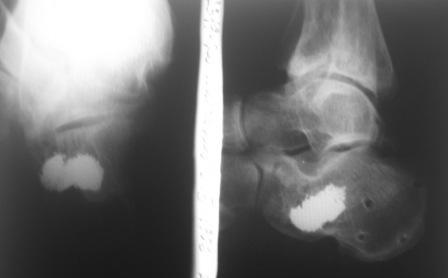

ЗДРАСТВУЙТЕ. ПОДСКАЖИТЕ ПОЖАЛУЙСТА 2 МЕСЯЦ НАЗАД Я УПАЛ С 4ГО ЭТАЖА-СЛОМАЛ ПЯТКУ. МНЕ СДЕЛАЛИ ОПЕРАЦИЮ, С ТАЗА ВЗЯЛИ КОСТЬ И ВСУНУЛИ В ПЯТКУ. ВРАЧИ ПРОМУЧАЛИ МЕНЯ ПОЧТИ 2 МЕСЯЦА И В ОКАНЦОВКЕ НЕ ДАЛИ ГАРАНТИИ ЧТО Я СМОГУ НАСТУПАТЬ НА НЕЕ И ЧТО ВОЗМОЖНЫ ЕЩЕ ОПЕРАЦИИ. СЕЙЧАС Я НАХОЖУСЬ ДОМА НА ЛЕЧЕНИИ С СПИЦАМИ В ПЯТОЧНОЙ КОСТИ. ВРАЧИ НЕ МОГУТ СКАЗАТЬ КОГДА Я СМОГУ ХОДИТЬ.ЧТО МНЕ ДЕЛАТЬ В ТОЙ СИТУАЦИИ?

Фото0046.jpg